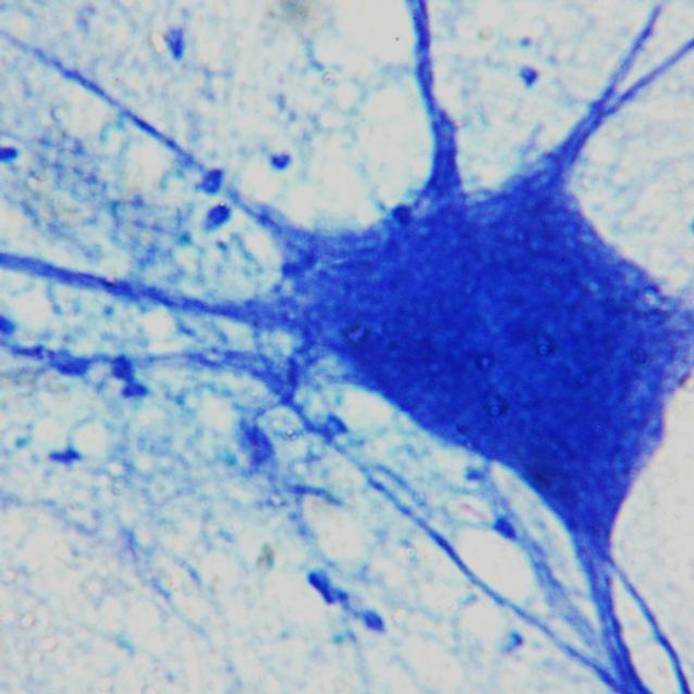

Neurons in the brain under a microscope

BSc (Hons) Mental Health Nursing

Mental Health Nursing students are encouraged to develop skills in independent learning, critical analysis, leadership, management, and decision-making.

Neuron cell in the brain under a microscope

BSc (Hons) Mental Health Nursing (Degree Apprenticeship)

This Nursing Degree Apprenticeship will equip you with the knowledge, skills, and behaviours necessary for registration as a Mental Health Nurse.